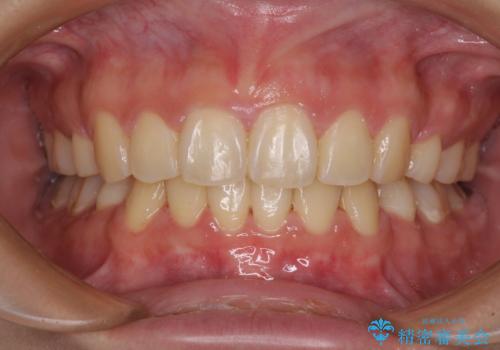

インビザラインによる矯正治療は、どれだけマウスピースを外す時間を短くできるかが成功の鍵となりますが、抜歯矯正ではよりシビアに要求されます。

こちらの患者様は、1日22時間以上を厳守してくださり、3年強で終えることができました。